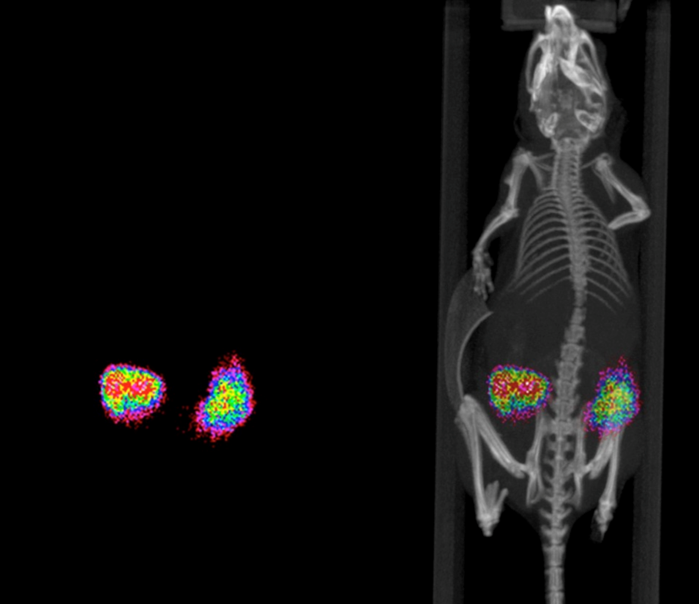

The SmART+ system, with the integrated BLI module, provides enhanced localized targeting with x-ray imaging and 3D-bioluminescence to improve sub-millimetric accuracy.

- Employs DOT to place center of mass of the light signal

- Overlays BLI signal onto DRR

- Performs multiple, optical projections acquired at different angles and wavelength filters

- Obtains surface mesh obtained from CT images